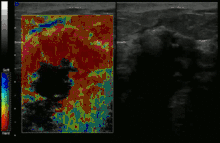

سونوگرافی

در این روش بوسیله انجام دادن سونوگرافی میتوان به وجود بافت یا توده مخرب سرطانی پی برد.